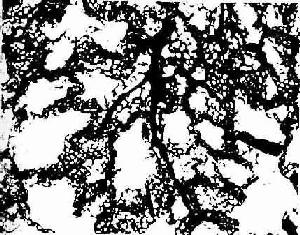

图14-17兔肺血管灌注示肺动脉分支及肺泡隔毛细血管网 ×400

↓肺动脉分支